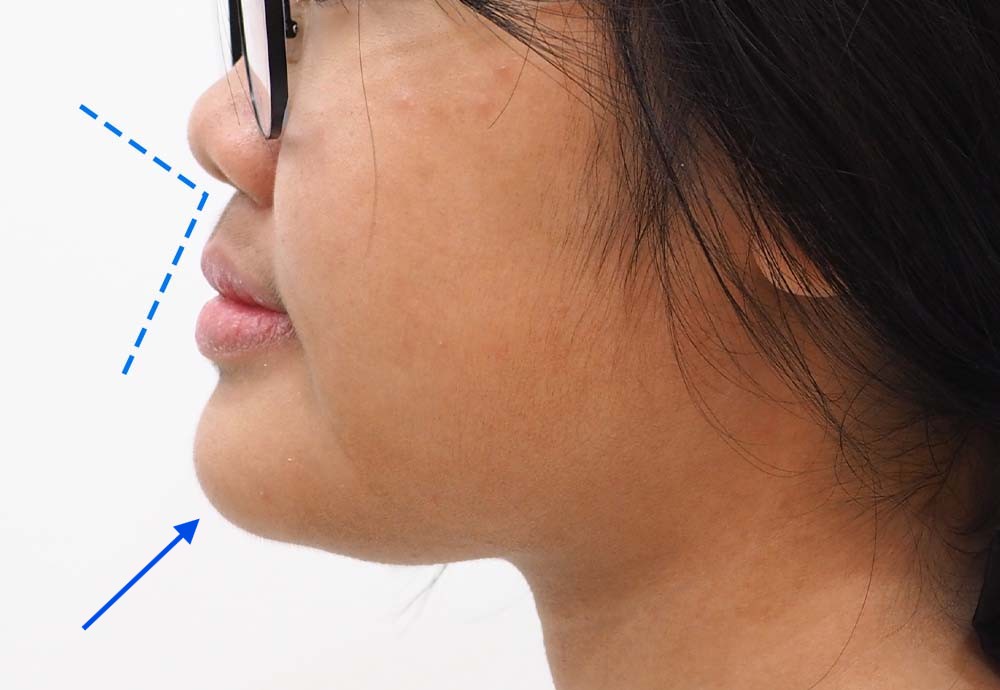

Dental Condition: Protruded side profile

In the right hands, braces can also subtly improve overall facial harmony and aesthetics (while correcting underlying jaw and tooth alignment issues).

Unlike metal braces that often rely on extraction to create space, clear aligners allow gentle arch expansion and digitally planned movement (distalization etc) to ensure the least compromise in facial profile.

Perfect if your facial profile makes you unsuitable for extraction.